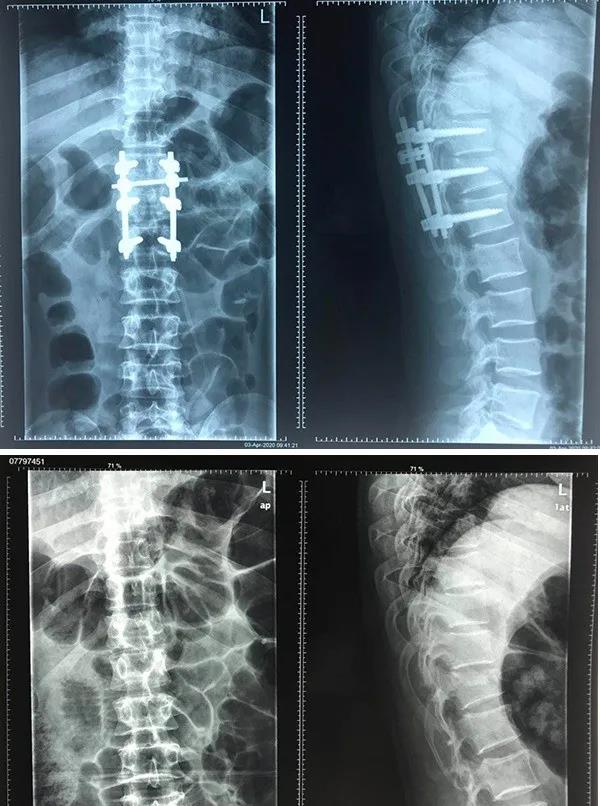

近日,從寧夏醫(yī)科大學(xué)總院獲悉,該院成功開展3D打印導(dǎo)板輔助置釘技術(shù)。此次手術(shù)的成功標(biāo)志著寧醫(yī)大總院骨三科在脊柱專業(yè)邁向了新的領(lǐng)域,填補(bǔ)了寧夏該類手術(shù)的空白。

據(jù)了解,30歲的張某,因不慎從高處跌落,導(dǎo)致腰部持續(xù)疼痛。經(jīng)寧夏醫(yī)科大總醫(yī)院骨三科團(tuán)隊(duì)診斷,為胸12椎體爆裂骨折。

寧醫(yī)大總院骨三科將數(shù)字化技術(shù)聯(lián)合3D打印手術(shù)導(dǎo)板應(yīng)用到手術(shù)中,對手術(shù)進(jìn)行虛擬設(shè)計(jì)、數(shù)字模擬手術(shù)、置釘導(dǎo)板的設(shè)計(jì)、預(yù)手術(shù)等計(jì)算機(jī)輔助設(shè)計(jì)在術(shù)前進(jìn)行充分設(shè)計(jì),制定出精準(zhǔn)化、最優(yōu)化的手術(shù)方案。

手術(shù)中,醫(yī)生常規(guī)暴露置釘節(jié)段椎板后,將術(shù)前制作的3D打印導(dǎo)板緊貼椎板放置,3D打印導(dǎo)板就相當(dāng)于一個(gè)“精準(zhǔn)定位器”,這樣就可以沿3D導(dǎo)板的置釘通道確定置釘點(diǎn)及方向,為患者快速精確置釘完成手術(shù),術(shù)后張先生腰部疼痛癥狀明顯緩解,效果良好。